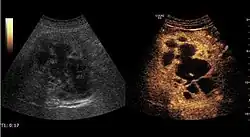

Benign focal nodular hyperplasia (CEUS). Gray scale examination (left) detects the lesion. CEUS examination (right) allows characterization of tumor nature based on central contrast enhancement and centrifugal dispersion.

It is a tumor developed secondary to a circulatory abnormality with abundant arterial vessels having a characteristic location in the center of the tumor, within a fibrotic scar. A radial vessels network develops from this level with peripheral orientation. The tumor's circulatory bed is rich in microcirculatory and portal venous elements. The incidence is higher in younger women and tumor development is accelerated by oral contraceptives intake. 2D ultrasound appearance is a fairly well-defined mass, with variable sizes, usually single, solid consistency with inhomogeneous structure. Rarely the central scar can be distinguished. Spectral Doppler examination detects central arterial vessels and CFM exploration reveals their radial position. CEUS examination shows central tumor filling of the circulatory bed during arterial phase and completely enhancement during portal venous phase. During this phase the center of the lesion becomes hypoechoic, enhancing the tumor scar. During the late phase the tumor remains isoechoic to the liver, which strengthens the diagnosis of benign lesion.